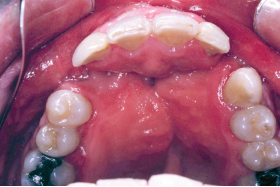

66 ○ Prosthodontic treatment planning should begin as early as possible within a cleft team setting. ○ A patient with a cleft often has significant dental issues that require intensive treatment. ○ The decision to move a canine into the position of a missing lateral incisor is as much a prosthodontic decision as an orthodontic one. ○ Long-term consequences of early treatment decisions should be considered before embarking on a particular dental treatment plan option. ○ Osseointegrated implants provide a high degree of success in replacing missing lateral incisors in properly selected patients. ○ Bone grafting is often required before implant placement for patients with clefts. ○ Many adult patients with clefts still require fabrication of a cleft speech bulb prosthesis. ○ Digital technology may greatly enhance and simplify prosthodontic care for the patient with a cleft. ○ The prosthodontist is an integral member of the cleft treatment team. Restorative dentistry or prosthodontic care for a patient with a cleft palate is often not considered until the patient has reached adulthood or until all the surgical and orthodontic care has been completed. At this point, the patient is referred to the prosthodontist to replace any teeth that are missing or are in need of restorations. Little consideration may have been given to the prosthetic or restorative treatment planning required to provide the optimum overall functional and aesthetic outcome for the patient. The patient with a cleft is best served by having a prosthodontist or restorative dentist become involved as early as possible in the treatment planning process. With the generally accepted principle that the team approach to management of patient with clefts provides the best results, the prosthodontist should become involved in treatment planning at the onset of cleft care, even as early as in infancy. The prosthodontist working with the surgeon, orthodontist, pediatric dentist, and other members of the cleft palate team at the onset of treatment is the most effective model of care. The prosthodontist must not be considered the treatment provider of last resort, to simply manage the unrepaired cleft palate or the failed pharyngeal flap or to merely replace missing teeth once all other phases of care have been completed.1 Several dental conditions are unique to patients with cleft palate. The most common finding in patients with unilateral clefts is the lack of the maxillary lateral incisor on the affected side. Duplication of the lateral incisor is not uncommon, however. Similarly, in patients with bilateral clefts, a second lateral incisor may be present on one or both sides of the maxillary dental arch, located on the premaxillary segment or on the lateral alveolar segments. This duplication of dental units often poses aesthetic challenges in the development of a natural appearance in the patient’s smile. Teeth adjacent to the cleft are often hypoplastic and dysmorphic in form. Prosthetic intervention may be required to provide balance and symmetry in the development of an aesthetic, as well as functional, final tooth arrangement. These teeth may be either larger or smaller than the tooth would normally be in an individual without a cleft. Consideration should be given to the selective extraction of teeth that will not enhance the long-term functional or aesthetic outcome. Therefore the orthodontist and prosthodontist must work closely together in establishing a symmetrical and balanced tooth arrangement while orthodontics are underway, rather than waiting for the “final” tooth position determined solely by the orthodontist. The dysmorphic shape and malposed position of teeth, combined with the increased tendency for mouth breathing, greatly increases the potential for dental caries in this patient population.2 The introduction of fixed or removable orthodontic appliances (or both) increases the potential for plaque accumulation and makes oral hygiene measures more challenging. Patients with clefts have a higher incidence of dental caries. These patients in particular should be thoroughly instructed on the proper methods of daily oral hygiene. Professional dental prophylaxis and examinations should be increased from the usual regimen of twice a year to a minimum of three times per year during the childhood and adolescent years, and perhaps even more frequently while they have fixed orthodontic appliances in place. Early prosthodontic interventions, such as placement of a fixed dental prosthesis to restore badly decayed teeth or to replace missing teeth, must take into consideration the presence of enlarged pulp chambers in the younger patient, thereby making either a carious or mechanical pulpal exposure more likely. Patients and their parents should be advised of the increased risk potential for the need for endodontic therapy for teeth that require extensive restorations. Every attempt should be made to keep tooth preparations for composite restorations, veneers, or crowns as conservative as possible in young patients. An adequate amount of tooth structure should be reduced to provide for physiologic tooth forms in the final restorations. These restorations should not increase the amount of plaque retention or compromise gingival health. In addition to the unique dental conditions that exist in patients with clefts, other important oral factors must be taken into consideration when providing prosthodontic care. A meticulous examination of the hard and soft tissues of the oral cavity, with particular attention paid to the possible presence of small or pinpoint sized fistulae (Fig. 66-1), is necessary. Dental impression material may be trapped in an unrecognized fistula or be pushed into the nasal cavity. The removal of this material may be difficult or impossible without nasal exploration. The presence of an unseen fistula may be discovered by pinching closed the patient’s nostrils and directing the patient to attempt to blow air out through the nose in a Valsalva maneuver. A high-pitched “hissing” sound may be heard or bubbling of mucous or saliva may be seen if a fistula is present. The presence of postoperative palatal scarring tends to produce posterior arch width collapse and the recurrence of a posterior crossbite if retainers are not fabricated and used regularly by the patient who has completed prosthodontic care to replace missing anterior teeth. Although a fixed dental prosthesis may serve to maintain tooth position in the anterior maxilla, unless the prosthesis is large enough and encompasses enough teeth to extend to the maxillary molars, orthodontic relapse, arch-width collapse, and redevelopment of a crossbite are likely. Fig. 66-1 Oronasal fistula at the junction of the primary and secondary palate. At cleft centers that use presurgical infant orthopedics (PSIO), such as nasoalveolar molding (NAM), the management of early infant oral and nasal molding may be undertaken by the orthodontist, prosthodontist, or pediatric dentist on the team, if the practitioner has been trained in the technique.3 The early use of PSIO appliances was initially advocated by a prosthodontist.4 In helping to manage the infant undergoing presurgical orthopedic care, the prosthodontist can become familiar with the development of the patient’s oral structures from the earliest onset of care. Children who have had a successful repair of their cleft have unique factors that should be taken into account as they grow and progress through orthodontic care and eventually into prosthodontic care. After a successful repair of the alveolar cleft, with or without a gingivoperiosteoplasty (GPP), the decision must be made before the eruption of the adult canines as to whether autogenous alveolar bone graft surgery is indicated. This determination is often made at many cleft centers by the orthodontist or surgeon alone, as is the decision to move the adult canine into the position of the missing lateral incisor. These decisions are ideally made in the setting of the cleft team, including the input of the prosthodontist who will ultimately be responsible for restoring, both functionally as well as aesthetically, the teeth in that area. This requires early collaboration between the prosthodontist and the orthodontist to determine the treatment option best suiting each particular child as they progress through their dentofacial development. A variety of orthodontic-prosthodontic pathways may be pursued. At the Institute of Reconstructive Plastic Surgery at New York University Medical Center, the orthodontic-prosthodontic evaluation usually begins at approximately 8 years old. The determination regarding what is needed to establish a solid and stable posterior occlusion is made while developing a maxillary dental midline that is as closely coincidental with the facial midline as is possible. Consideration will then be given to establishing an intact maxillary alveolus (if this has not already been accomplished through an early GPP after NAM therapy). The positions of the remaining teeth, relative to the available space, are then worked out using a series of diagnostic wax mockups as the child ages and until early adulthood. Often, the decision of whether a missing lateral incisor will best be restored with a transported canine or an osseointegrated implant is not made until the age of 16 years (Fig. 66-2).